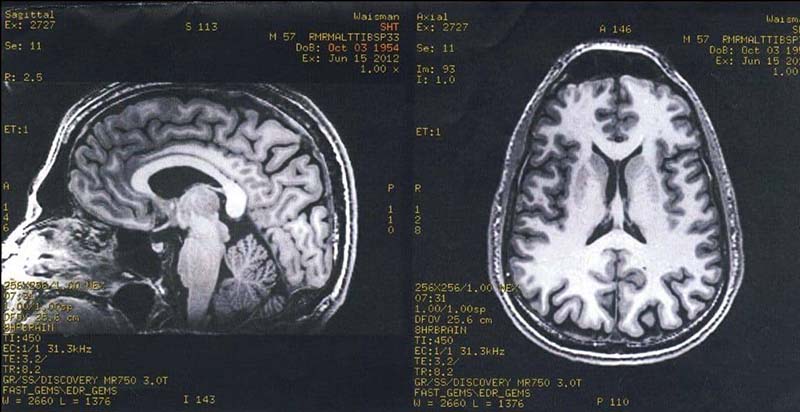

e finished that up and I got up to get ready for the lab. The technician at the computer screen behind me in the picture said, “Steve, what’s your middle initial?” I said, “H. Stephen Horton Tibbetts.” He hesitated a moment, tapped something into his keyboard, hit return, and I saw the letters “SHT SCAN” on the top of his monitor. (Later on, at dinner, Mom laughed and said, “Oh. Sorry. Sorry about that. I never thought about that when we named you.”)

I popped in some ear plugs they gave me (the machine was loud) and put the respiration belt around my middle. I laid down on the sliding panel, the technicians attached the heart monitor and other devices to my hands, and they slid me into the machine. It started whirring and clunking. The technicians closed the door to the lab and went back into the control room. My heart was beating really fast, and knowing that Antoine and the technicians were monitoring my heartbeat made it speed up even more. We started. Open Presence. Burning. Focused Attention. Burning. “Put your hand in the box.” There were speakers inside the machine. Antoine occasionally asked, “How are you doing?” I always replied that I was doing fine. The machine was very loud, and I couldn’t really move my neck or head for quite some time. Amazingly, the burning pad did not leave a mark on my skin.

But he didn’t. The technician took our picture, and then Antoine and I spent some time in the control room talking. Richie came in, hugged me, and gave me an autographed copy of his book.

Into the machine

Done